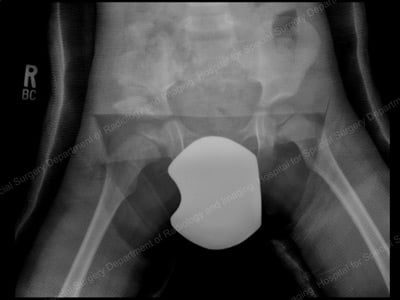

Preoperative view of a right hip dislocation, where the right leg appears shorter than the left.

Anterior-to-posterior (front-to-back) X-ray image, six months after open reduction with a realigned right hip.